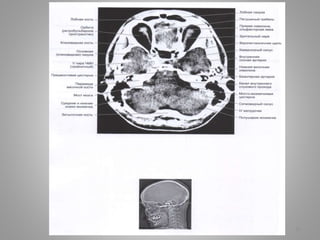

• #5 Оболонки спинного мозку. Шийний відділ.

• #9 Велика (мозочково-мозкова) цистерна (cisterna magna, c. cerebellomedullaris) – сама велика цистерна, яка обмежена мозочком, довгастим мозком та потиличною кісткою. Цистерна моста (препонтинна) - розташовується наперед від моста мозку, містить базилярну артерію. Зєднується позаду з мосто-мозочково-мозковою цистерною та субарахноідальним простором спинного мозку, попереду – з міжніжковою цистрною. Базальна цистерна (c. suprasellar) має п'ятикутну форму, включає міжніжкову цистерну (між ніжками мозку) і цистерну перехреста (між перехрестом зорових нервів і лобними частками). Чотиригорбкова цистерна (вени Галена) (c. quadrigeminalis) розташовується між мозолистим тілом і мозочком; у її ділянці можуть розташовуватись субарахноідальні кисти Обвідна (охоплююча; по Синельникову - обхідна) цистерна (c. ambient) - канал неправильної форми, що проходить по бокам ніжок мозку і даху середнього мозку; сполучається з мостовою і міжніжковою цистернами спереду і чотирегорбиковою цистерною ззаду. Цистерна бічної ямки великого мозку (cisterna fossae lateralis cerebri) - розташовується в латеральній борозні великого мозку.

• #11 Передмостова цистерна (цистерна моста) розташовується наперед від моста мозку, містить базилярну артерію. Зєднується позаду з мосто-мозочково-мозковою цистерною та субарахноідальним простором спинного мозку, попереду – з міжніжковою цистрною.

• #12 Білясередньомозкова цистерна: Чотиригорбкова цистерна (вени Галена) (c. quadrigeminalis) розташовується між мозолистим тілом і мозочком; у її ділянці можуть розташовуватись субарахноідальні кисти Обвідна (охоплююча; по Синельникову - обхідна) цистерна (c. ambient) - канал неправильної форми, що проходить по бокам ніжок мозку і даху середнього мозку; сполучається з мостовою і міжніжковою цистернами спереду і чотирегорбиковою цистерною ззаду.

• #13 Міжніжкова цистерна

• #14 Міжніжкова цистерна Охоплююча цистерна Чотирегорбикова цистерна Верхня цистерна мозочка

• #15 Велика цистерна

• #16 Передмоства цистерна Мосто-мозочкова цистерна

• #17 Міжніжкова цистерна Базилярні цистерни

• #18 Охоплююча цистерна

• #19 Охоплююча цистерна